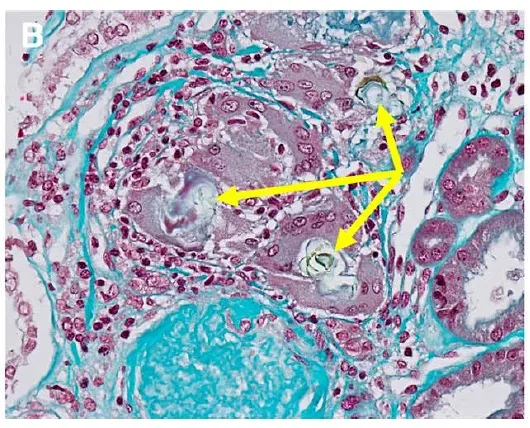

Uma causa incomum de hematúria glomerular intermitente!

Uma causa incomum de hematúria glomerular intermitente!

Hematúria pós infecção, caso clínicos para auxiliar no entendimento de causas glomerulares comuns e raras...